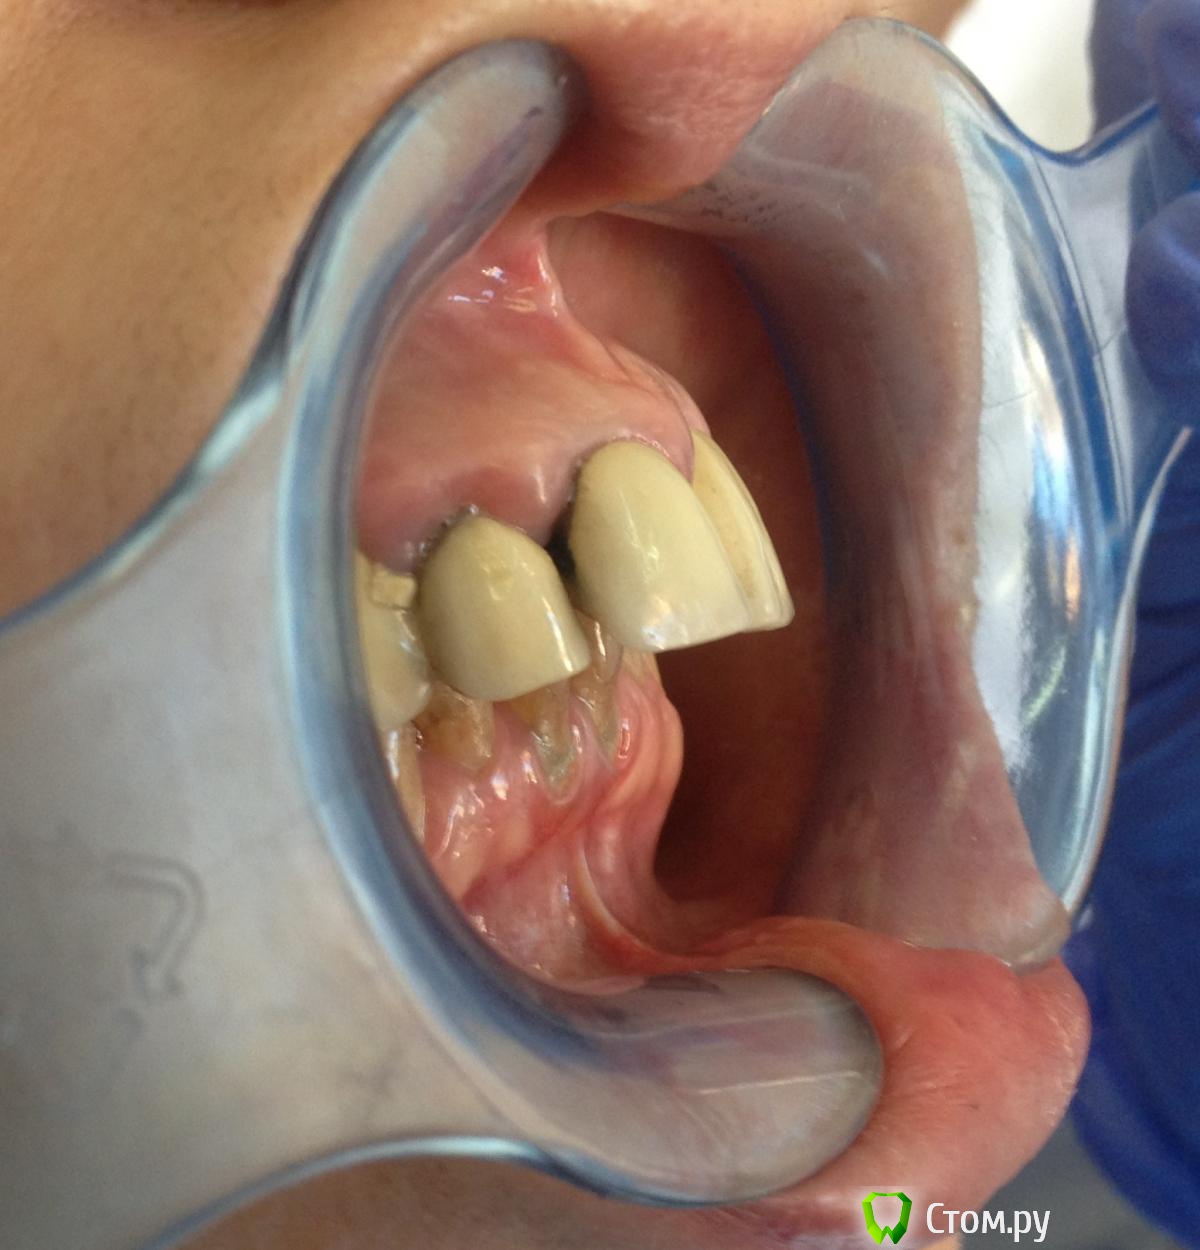

MaxDok Опубликовано 31 января, 2014 Поделиться Опубликовано 31 января, 2014 Пациент, 45 лет. Жалобы на эстетически не состояельные реставрации . Хочет красивую улыбку С чего посоветуете начать коллеги? Ссылка на комментарий

Beznika Опубликовано 13 февраля, 2014 Поделиться Опубликовано 13 февраля, 2014 Жесть Для начала чистку назначьте Что там с 37? или 36... Ссылка на комментарий

MaxDok Опубликовано 13 февраля, 2014 Автор Поделиться Опубликовано 13 февраля, 2014 Пациентка перезаписалась , пуржило у нас , завтра снимаю конструкцию с вч,примерю мокап, 36 на удаление. Ссылка на комментарий